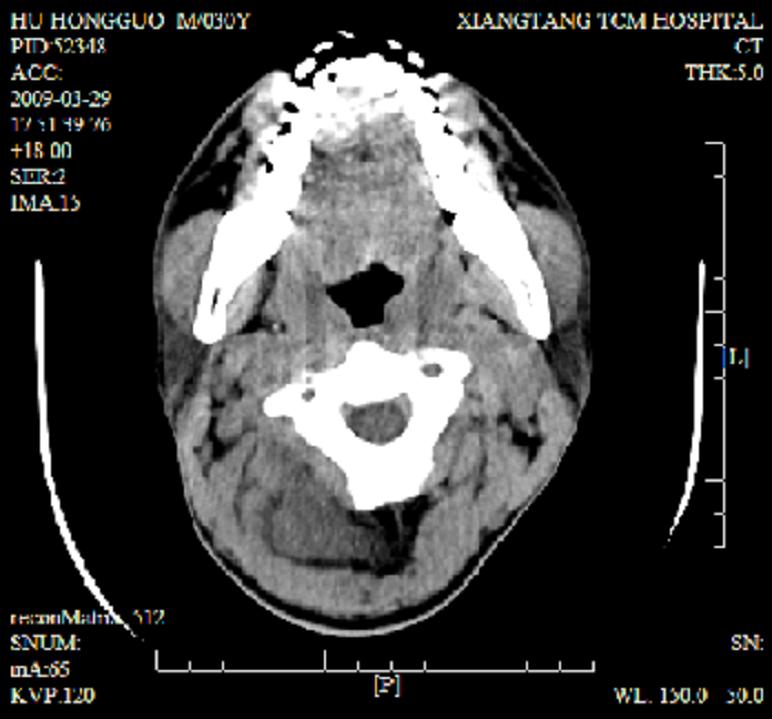

标题: CT19102:颈部肿块

男30y发现肿块3年

多处囊实性肿块,形态欠规则有一定形态,内见点状钙化,以囊变为主,增强后轻度强化,首先考虑神经源性肿瘤如鞘瘤,不除外脉管源性肿瘤如淋巴管瘤(见缝钻及囊性区域太多,如果合并感染完全可以这个影像表现),和海绵状血管瘤,但是血管瘤不太支持因为强化特征和病灶形态不典型.

右侧椎前间隙后部肌间、皮下囊性为主病变,可见分隔和点状钙化,分隔和壁呈轻度环形强化,大部分无强化。形态不规则,有钻缝特点。考虑1 淋巴管瘤合并感染2 血管平滑肌脂肪瘤3 表皮样囊肿4 不除外海绵状血管瘤。